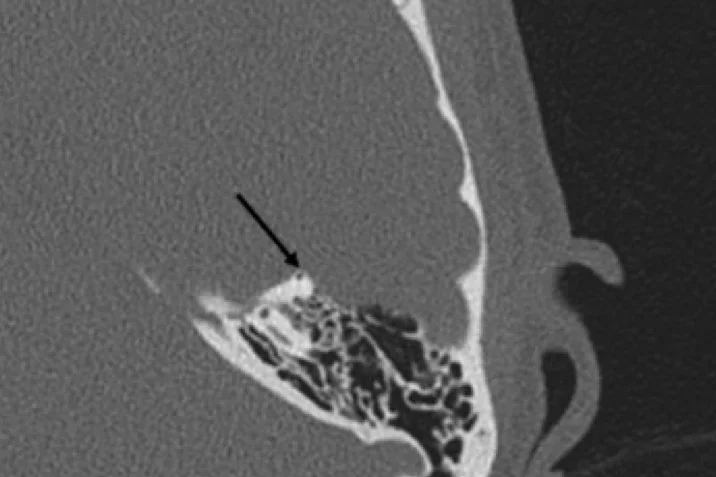

High-resolution computed tomography, which demonstates dehiscence of the left superior semicircular canal